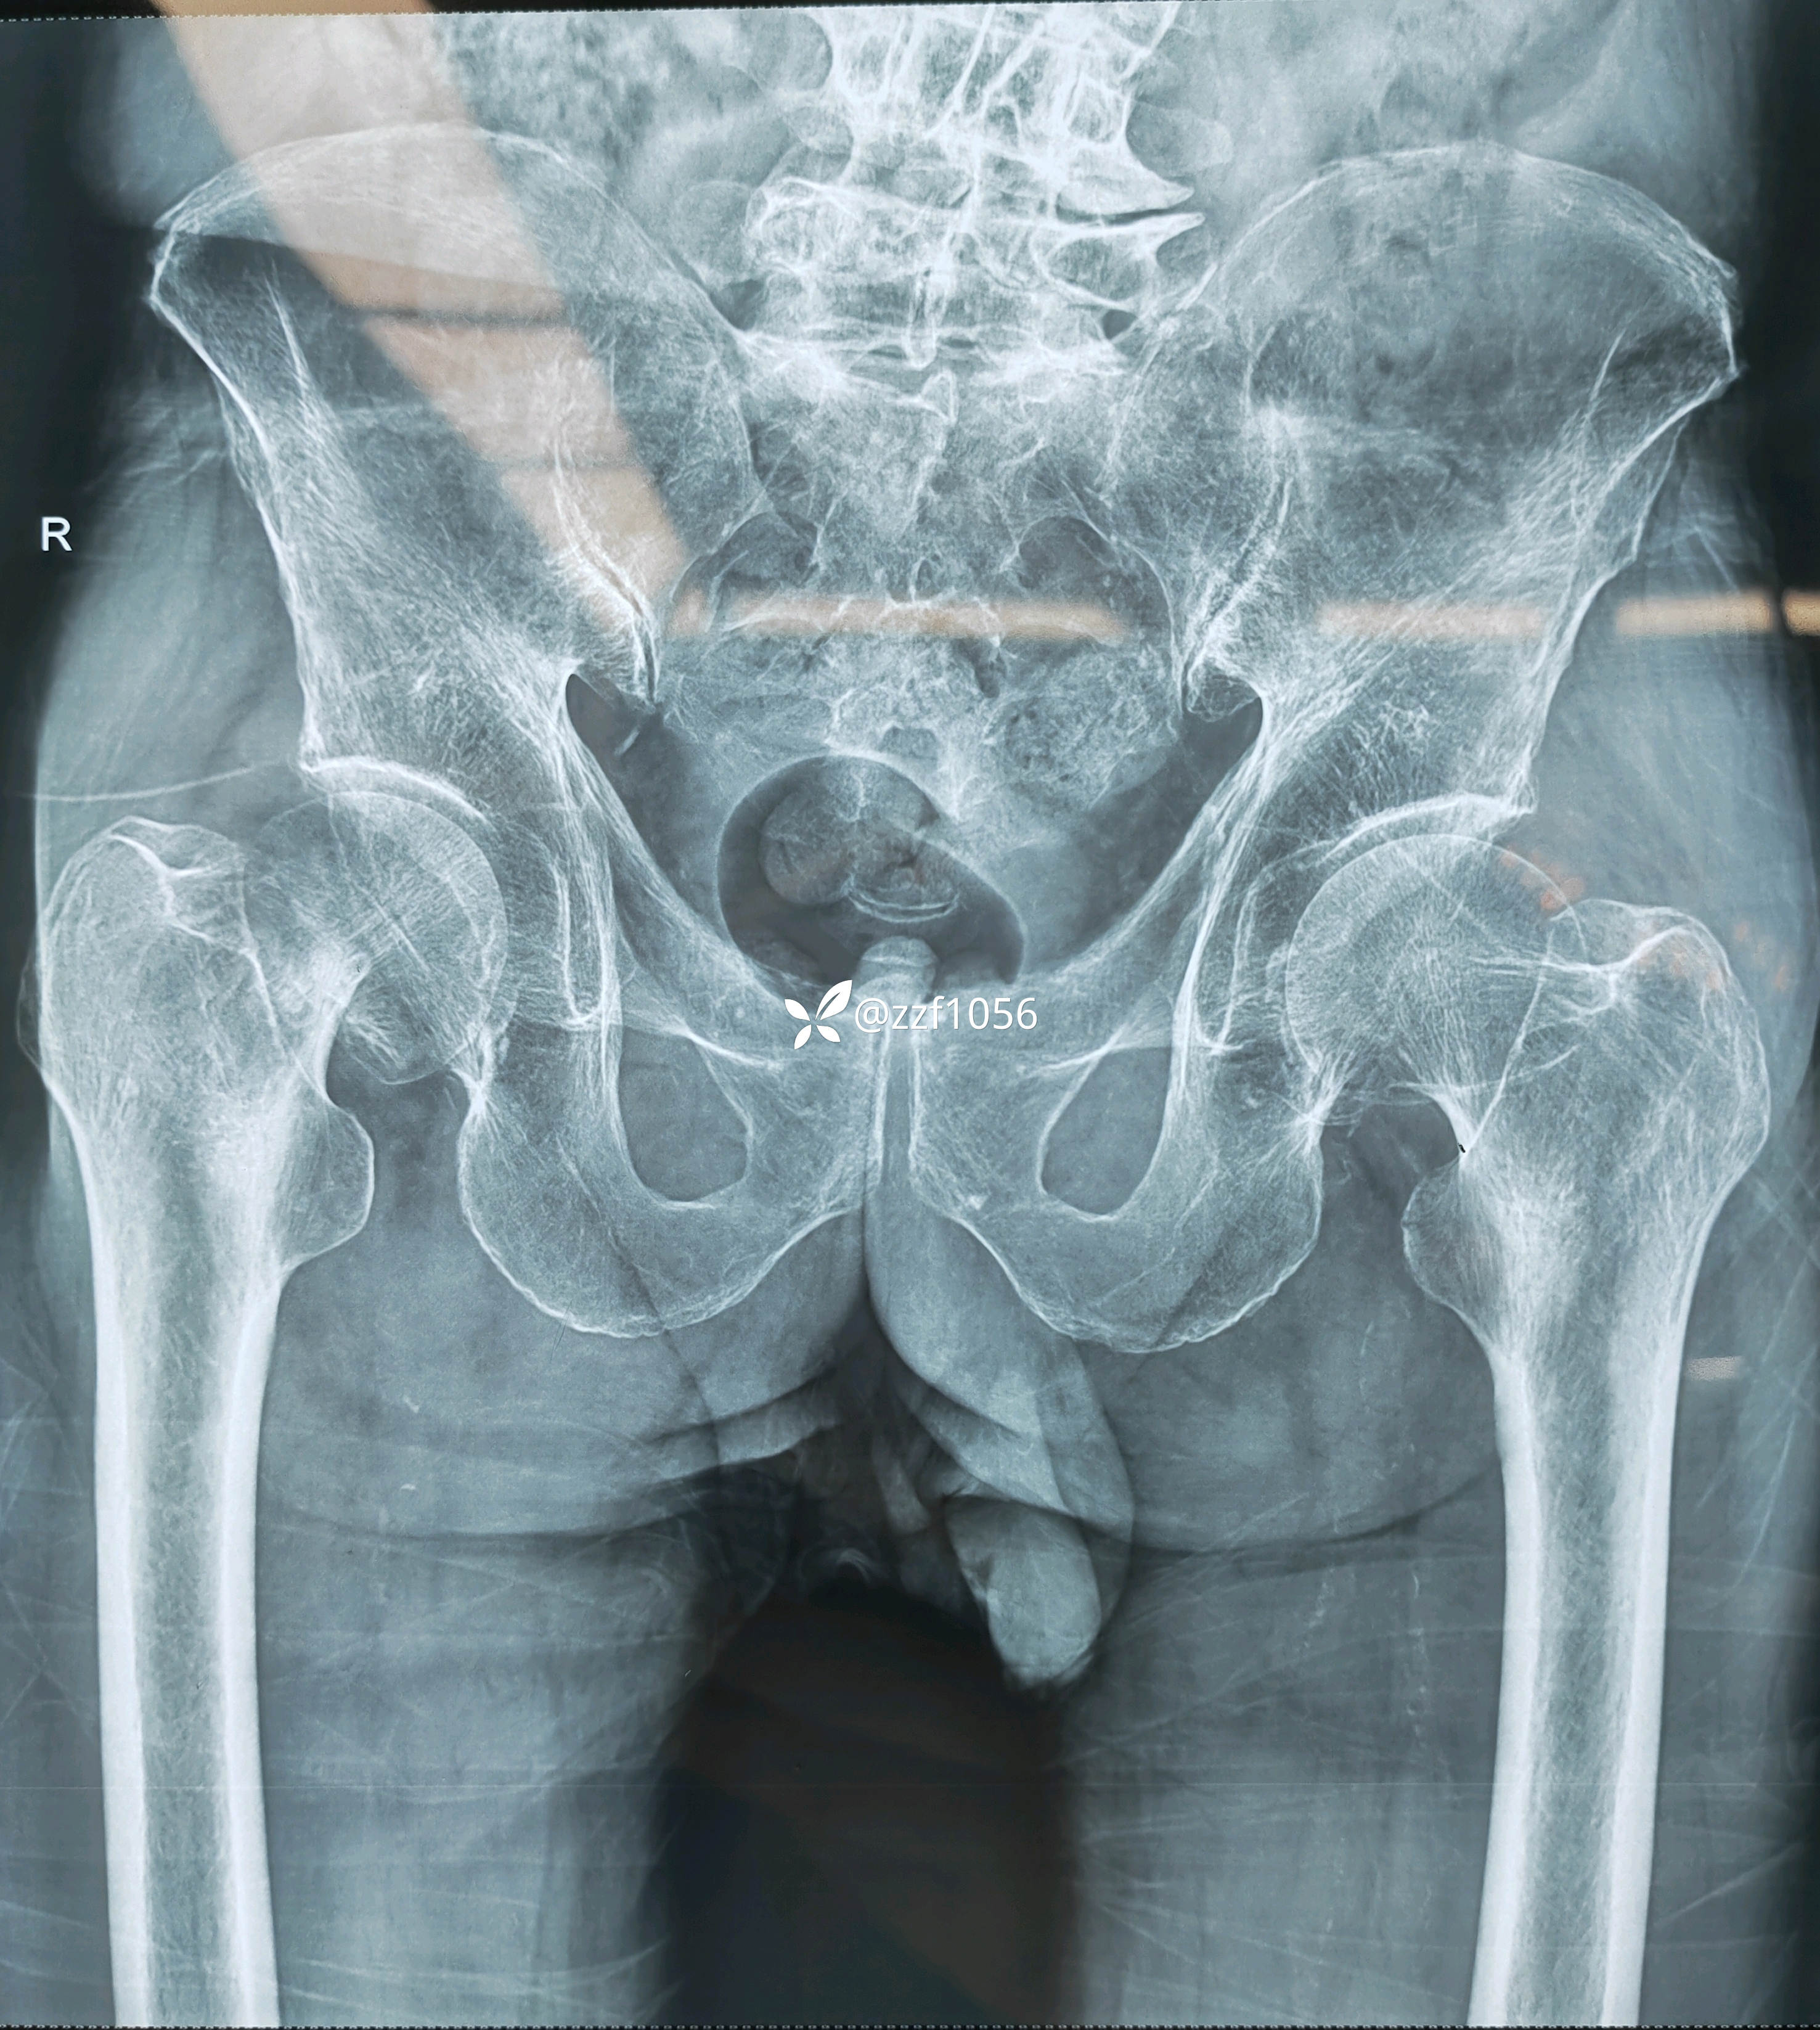

患者男80岁,摔伤右髋疼痛5天,入院。

5天前家里摔伤,附近医院摄片显示右侧股骨颈骨折,因身体状况不好回家保守治疗,疼痛无法耐受再次赴当地县医院就诊,评估身体状况后告知手术风险较大,后经熟人介绍转来我院就诊。

入院诊断:右侧股骨颈骨折